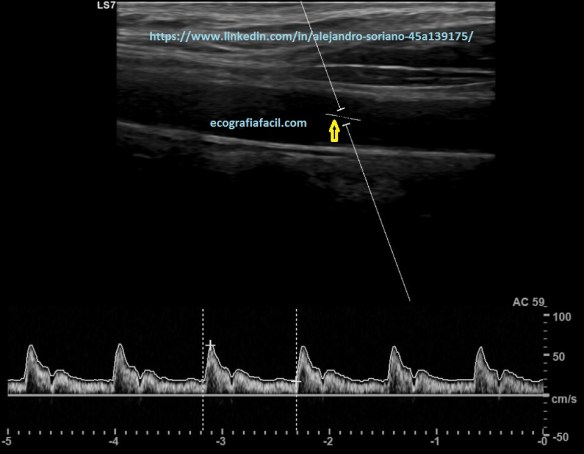

Como vemos en las tres imágenes con distintas angulaciones obtendremos un espectro bastante decente pero no en todos los casos obtendremos datos suficientemente fiables.

En la imagen 11 hemos conseguido poner la línea paralela pero a cambio de una angulación superior a 60º; por tanto, tendremos que “jugar” con la angulación del vaso y la del propio Doppler para tener un ángulo inferior a 60º y que quede la línea paralela a la pared del vaso como tenemos en la imagen 12. Esto nos permitirá tener la tranquilidad de que los datos obtenidos serán más fiables.

- Frecuencia de repetición de pulsos o escala de velocidades: la ajustaremos a las velocidades del estudio.

- Con un rango de velocidades altas tendremos un espectro demasiado pequeño, lo que nos dificultará su evaluación; un rango demasiado bajo producirá “aliasing”.

- El comando que buscaremos será el de la «escala»